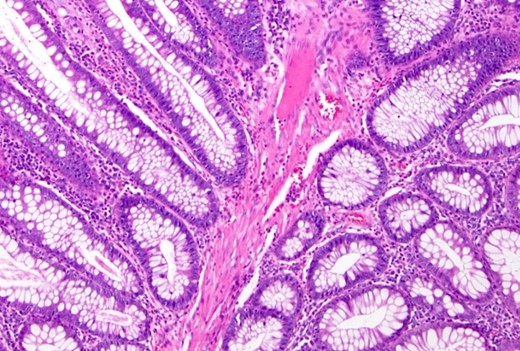

The decision was made to proceed with laparotomy. Intraoperatively, upon midline laparotomy, a jejuno-jejunal U-shaped volvulus with intussusception was initially identified (Fig. 3). Following multiple maneuvers to manually reduce the intussusception, ~80 cm of gangrenous jejunal intussusceptum was resected, followed by end-to-end anastomosis. Examination of other segments of the small and large bowel revealed two ileal polyps, with dimensions of ~3 × 5 cm2 and 2 × 2 cm2, respectively (Fig. 3). Each polyp was resected, and the surgical sites were repaired primarily. Following closure of the abdomen, the patient was transferred to the intensive care unit for postoperative monitoring. The excised mass was sent for histopathological analysis, which confirmed the presence of typical hamartomatous polyps. Postoperatively, the patient demonstrated satisfactory progress, tolerated oral feeding and was discharged on the seventh day after surgery. Two months later, diagnostic endoscopy revealed multiple polyps in the large bowel measuring 5–15 mm (Fig. 4), without evidence of intussusception. These polyps were removed via endoscopic polypectomy. Histopathological examination of the removed polyps confirmed the presence of characteristic PJS polyps, displaying a branching framework of connective tissue and smooth muscle lined by normal intestinal epithelium (Fig. 5). Subsequently, a detailed family history revealed similar skin lesions in the patient’s uncle.

Histopathological study: showing an edematous appearance of the intestinal mucosa with inflammatory lymphocytes and histiocytes.